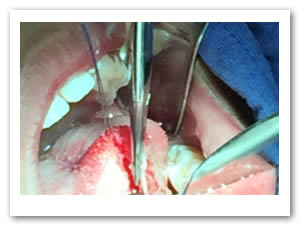

• Se eliminó el frenillo en su totalidad  con la ayuda de tijeras iris recta y hoja de bisturí del No. 15 así como todo el tejido residual fibroso correspondiente al frenillo. Se realizó genioplastia con pinza de mosco y disección roma para liberar adecuadamente la inserción frénica hasta la cara lingual de los incisivos inferiores. (Figuras  7, 8 y 9)

Figuras 7 y 8. Eliminación total del frenillo y genioplastia

Figura 9. Resultado obtenido después de genioplastia